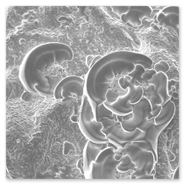

1. Scanning Electron Microscopy Processing unit

Electron Microscopy (EM): Basically two types:

1. Transmission Electron Microscope2. Scanning Electron Microscope

1. Transmission Electron Microscope (TEM) processing unit2. Scanning Electron Microscope (SEM) processing unit3. Ultra Microtome and Histopathology4. Experience in the field of specimen preparation for past 16 years